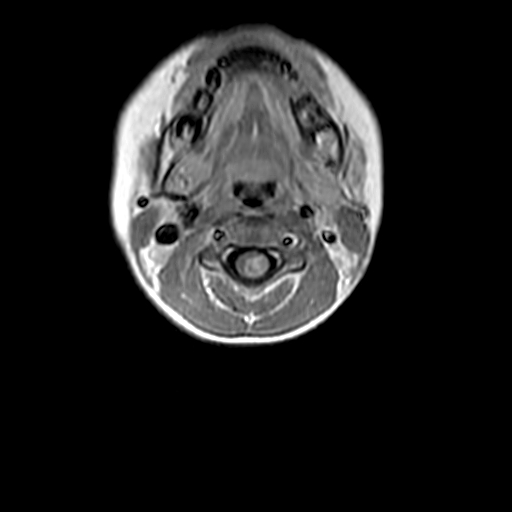

患者,男,5岁。左侧肢体无力10余天,无其他不适,头颅ct未见明显异常。

颈髓局限性增粗,呈混杂t1、混杂长t2信号,增强后不均匀强化。考虑胶质瘤。

髓内肿瘤,呈囊实性,增强实怀部分有强化,多考虑星形胶质瘤,不除外室管膜瘤